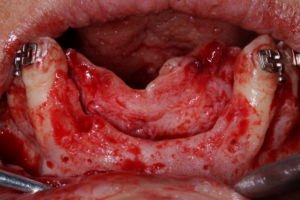

Após a extração dos referido dentes, o retalho de espessura total foi elevado para exposição completa do defeito ósseo. Veja a discrepância dos picos ósseos medial e distal na posição dos laterais, e a anatomia complexa do defeito.